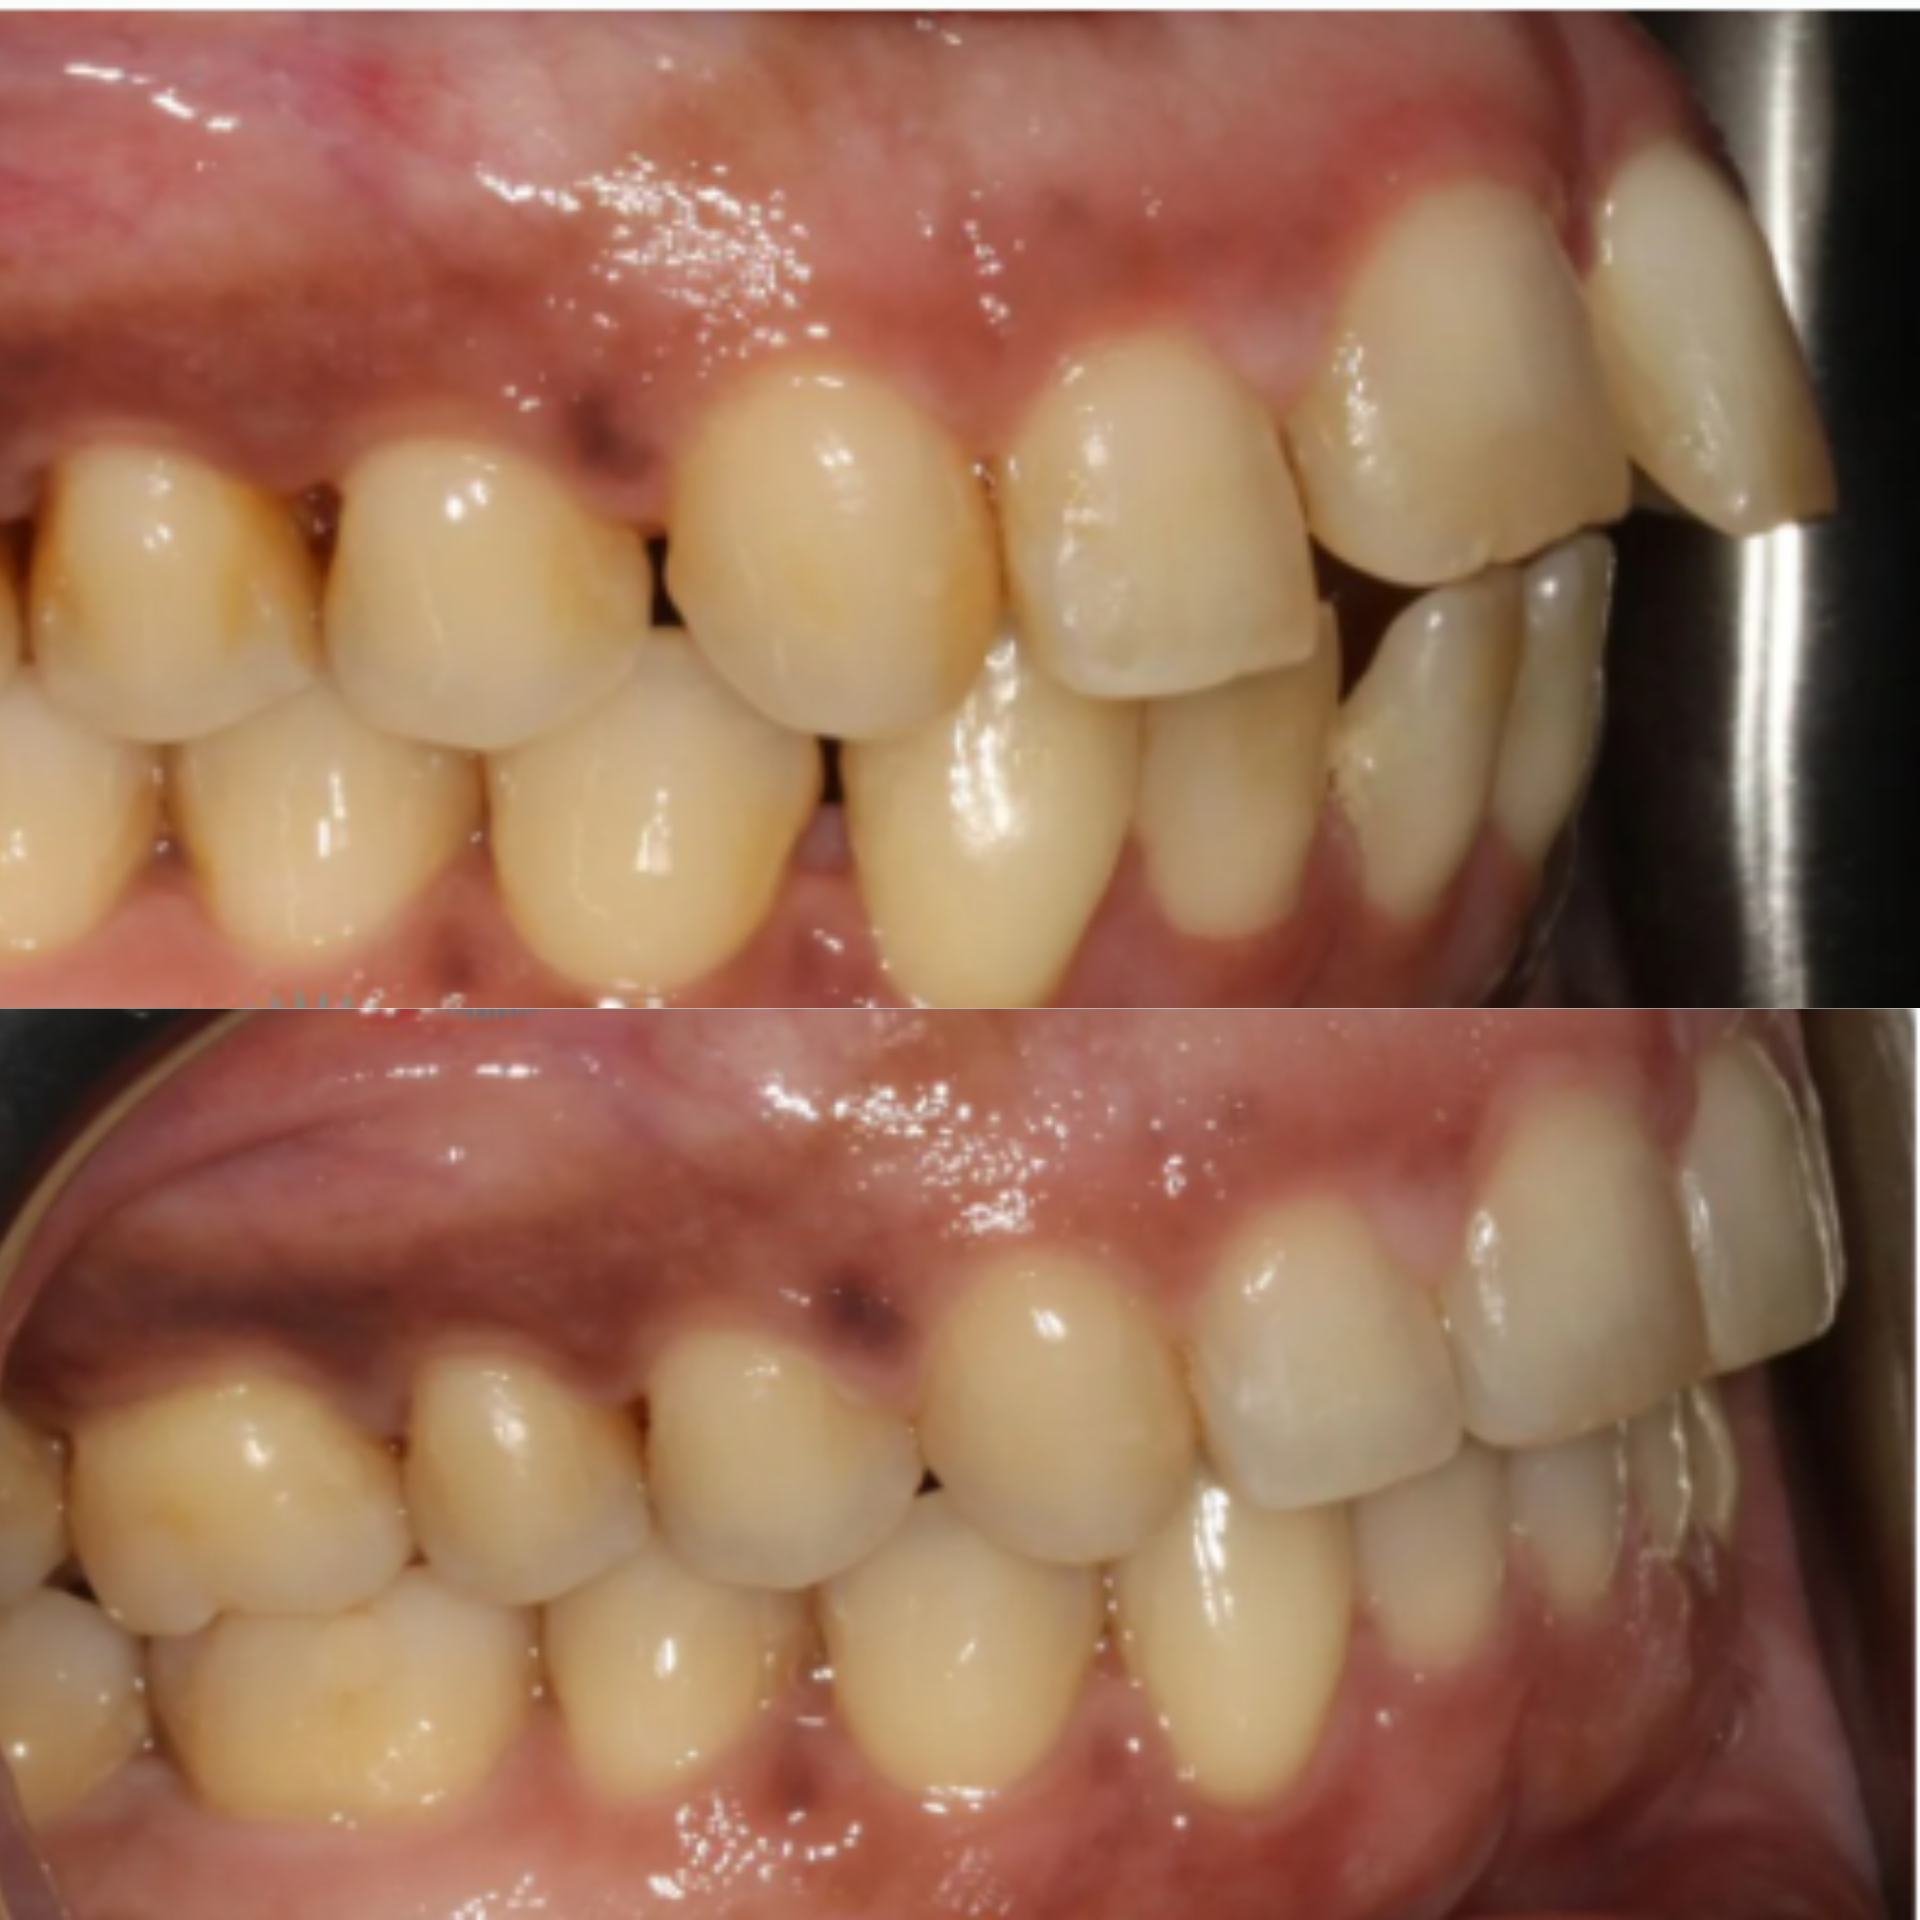

At Elite Dental Group, we provided emergency care that included root canal treatment on the upper central incisors. Dr. Satish Palayam performed an immediate implant placement for the right lateral incisor and completed a crown lengthening procedure on the palatal side of the right central incisor to support proper restoration. A provisional bridge was then placed to maintain both function and esthetics throughout the healing phase.

After a four month healing period, the final crowns were placed on the central incisors, and the implant for the right lateral incisor was successfully restored and finalized.